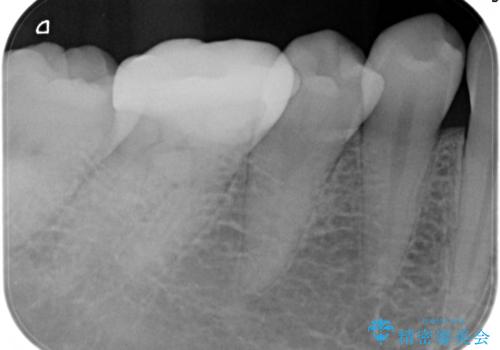

【根管治療】噛んだら痛い。ズキズキ痛い

- 4日前から噛んだ時に痛むことを主訴に来院された患者様です。

歯髄壊死/症候性根尖性歯周炎の診断のもと、根管治療を行なっております。